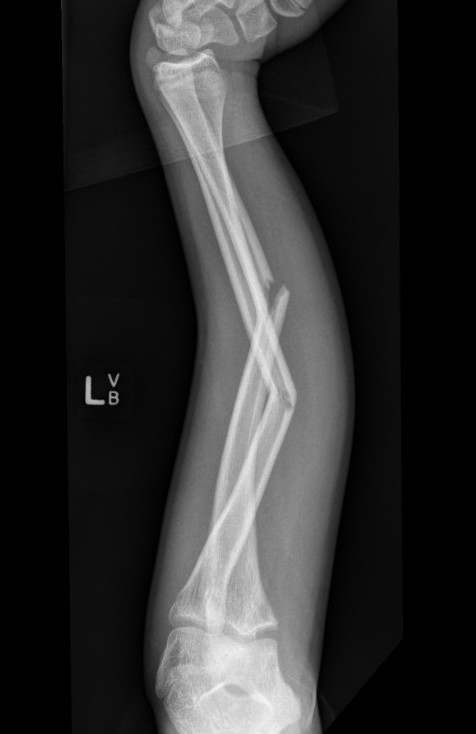

3. Intramedullary elastic nail

Advantage

- smaller scars with insertion

- easier to remove than plates

Disadvantage

- generally immobilized

- must be removed

- non anatomical reduction compared with plates with theoretical risk of loss supination / pronation

- risk of extensor tendon rupture due to prominence of nails at insertion sites

TENS technique

Technique

Radius (typically first as more difficult to reduce)

Entry point with awl 2 cm proximal to distal physis

1. Radial styloid / distal lateral entry

- ensure radial nerve / cephalic vein, 1st extensor compartment protected

2. Listers tubercle / dorsal entry

Elastic Nail size

60 - 70% of the intramedullary canal

Typically 1.5 - 2.5 mm

Fracture reduction

Avoid passing nails incorrectly multiple times as may cause compartment syndrome

Bend tip of elastic nail

May need small open reduction

Cut nail

Withdraw 1 cm, cut with endcutter, then advance

Ulna (usually reduced after radius fixation)

Entry point 2 cm distal to apophyseal plate

1. Proximal lateral

- avoids ulna nerve

3. Distal medial

Postoperative

Cast in supination to tighten interosseous membrane

Cast 6 weeks

Removal of TENS at 4 - 6 months once osseous union established